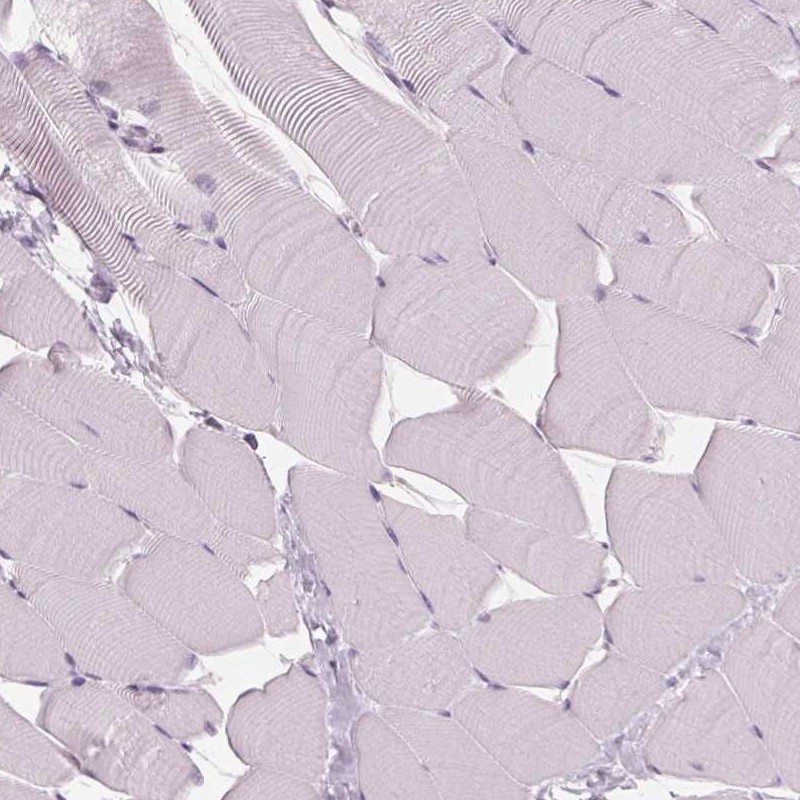

Immunohistochemistry analysis in human thyroid gland and skeletal muscle tissues using Anti-DNASE2 antibody. Corresponding DNASE2 RNA-seq data are presented for the same tissues.